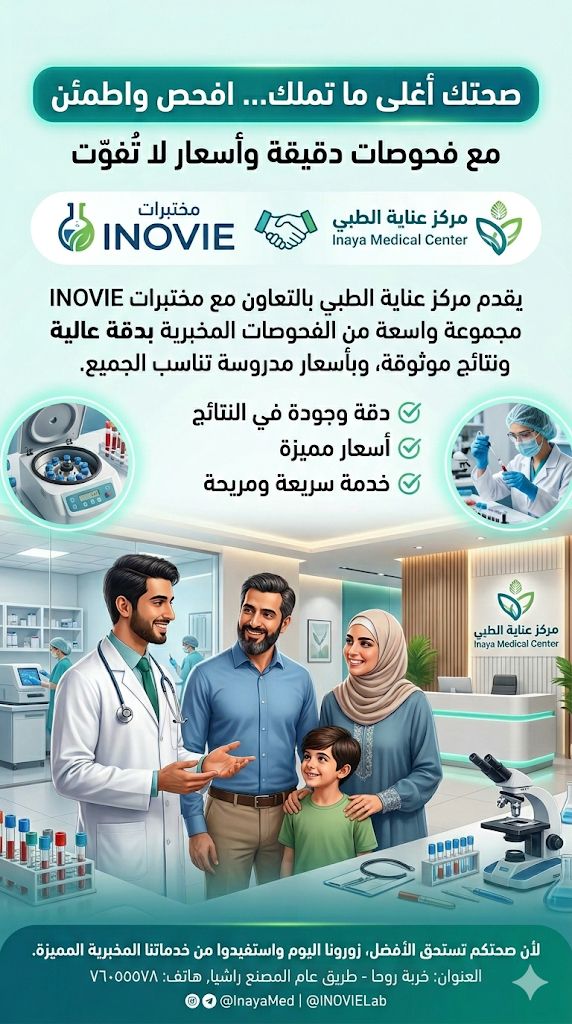

مركز عناية الطبي: دوام الأطباء والخدمات... مركز عناية الطبي: دوام الأطباء والخدمات – السبت 13 حزيران

مركز عناية الطبي: دوام الأطباء والخدمات...

مركز عناية الطبي: دوام الأطباء والخدمات – السبت 13 حزيران صيدلية حرمون

مركز عناية الطبي: دوام الأطباء والخدمات...

مركز عناية الطبي: دوام الأطباء والخدمات – الجمعة 12 حزيران صيدلية حرمون

مركز عناية الطبي: دوام الأطباء والخدمات...

مركز عناية الطبي: دوام الأطباء والخدمات – الخميس 11 حزيران صيدلية حرمون

مركز عناية الطبي: دوام الأطباء والخدمات...

مركز عناية الطبي: دوام الأطباء والخدمات – الأربعاء 10 حزيران صيدلية حرمون